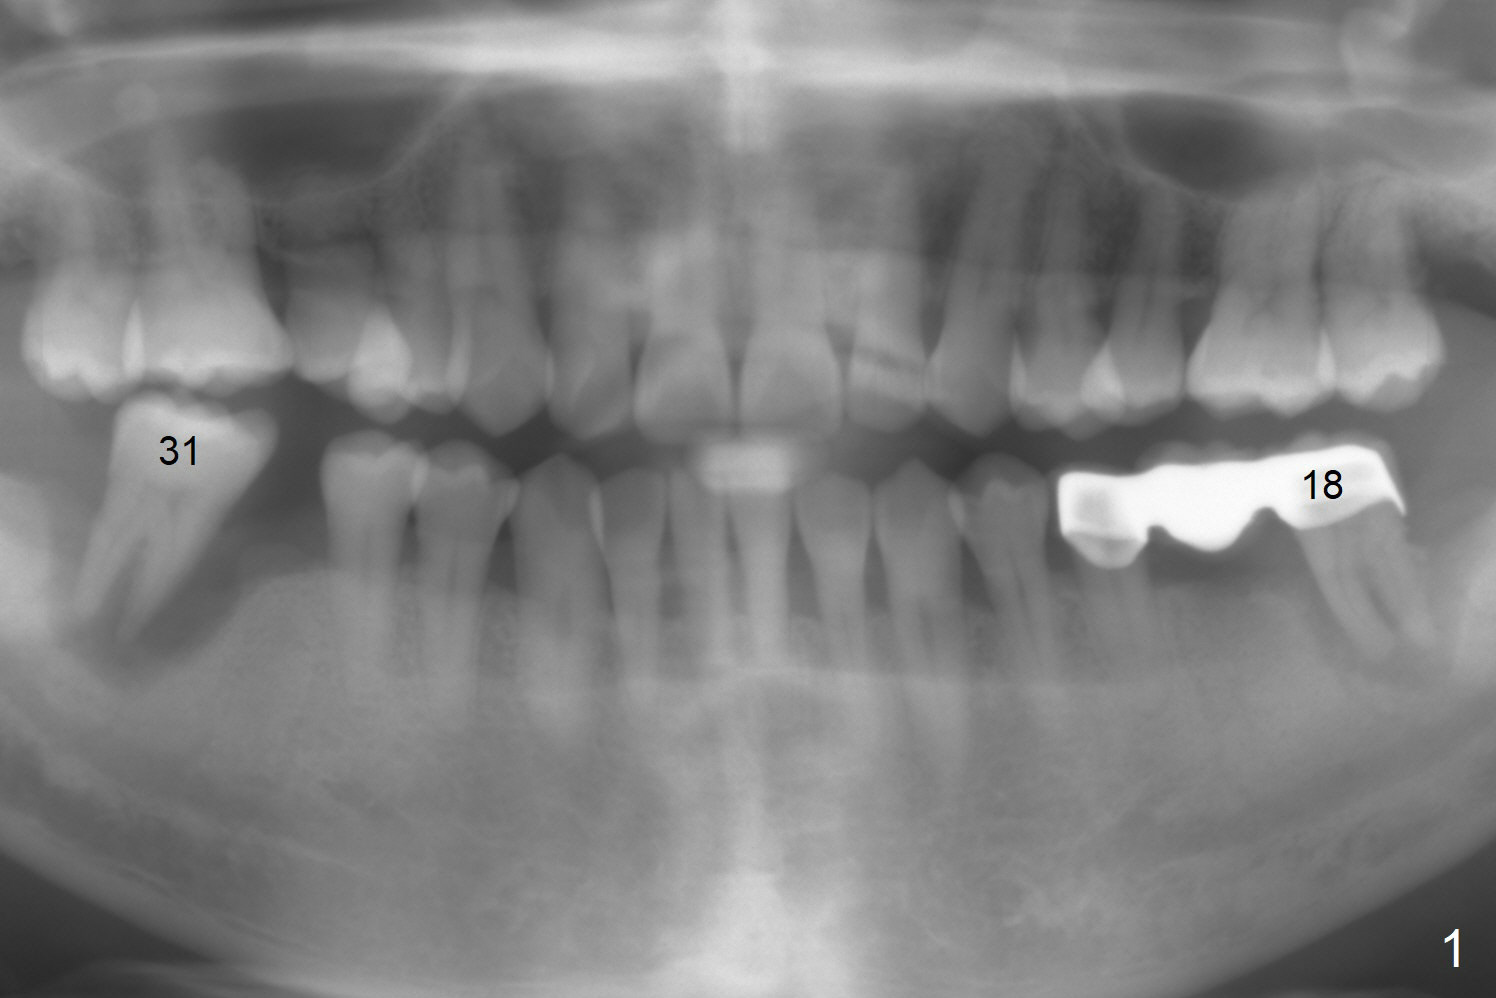

A 64-year-old man has discomfort with the lower left bridge and a loose tooth on the left (Fig.1). It appears that 4 implants are to be placed at #18,19,30 and 31. Since the tooth #4 and 13 are palatalized (Fig.2-4), the teeth #2 and 3 are mesialized (Fig.2 arrow). Besides, the ridge at #30 must be atrophic due to long termed edentulism. A small-diameter implant will be placed at #30 with premolar width (Fig.6-13), while the implant at #31 will be placed distal (arrow, as compared to Fig.2). To establish harmonious occlusion at provisional and final stages, the palatal slope of the mesiopalatal cusp of the tooth #2 will be adjusted (Fig.10).

Prepare 3 large pieces of gauze with the vasoconstrictor. If one of them is still too small for the socket, insert another piece of gauze without the vasoconstrictor for pressure hemostasis. Prepare PRF (x4) and Sinus Master Kit in case short stoppers are needed (Fig.12). CBCT taken immediately preop shows relatively wide ridge at #30 (Fig.14,16). The implant at #31 should be place in the distobuccal aspect of the socket (Fig.15,17): 2 mm drill with 7 mm stopper, 2.8 mm round drill at 5 mm (50 RPM) and 3.6 mm at 3 mm.